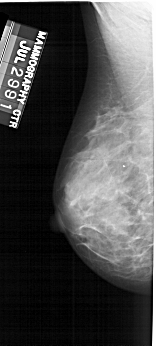

A_1734_1.RIGHT_CC

RIGHT_CC LINES 4696 PIXELS_PER_LINE 2236 BITS_PER_PIXEL 12 RESOLUTION 43.5 OVERLAY